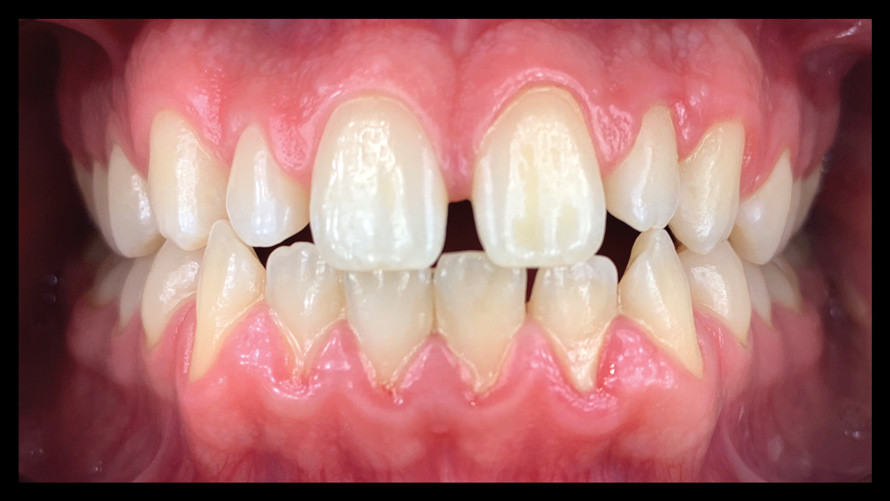

(9. through 11.) Preoperative esthetic case documentation using a smartphone and an EALS device.

Figure 9

Figure 10

Figure 11

One of the main advantages that smartphone cameras have over DSLR cameras is that nearly everyone is already very familiar with the technology; therefore, the incorporation of these devices into everyday practice does not require learning a new and unfamiliar skill set. The task of producing a series of high-quality clinical photographs for routine examinations (Figure 8), esthetic treatment planning (Figure 9 through Figure 11), or specialty care (Figure 12 and Figure 13) can be delegated with confidence to any staff member during the patient's initial office visit and will generally require less than 5 minutes of time to complete. When a DSLR camera is used, evaluation of the intraoral images either takes place on the small viewfinder built into the camera or necessitates the physical removal of the memory card from the camera to downloaded the images onto a computer for review. An added bonus of smartphone dental photography is that the phone's screen now replaces the much smaller viewfinder of a DSLR camera and provides the clinician with the ability to view and zoom into the patient images on a 5- to 6-inch, high-definition display.